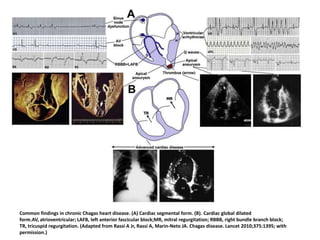

Common findings in chronic Chagas heart disease. (A) Cardiac segmental form. (B). Cardiac global dilated

form.AV, atrioventricular; LAFB, left anterior fascicular block;MR, mitral regurgitation; RBBB, right bundle branch block;

TR, tricuspid regurgitation. (Adapted from Rassi A Jr, Rassi A, Marin-Neto JA. Chagas disease. Lancet 2010;375:1395; with

permission.)